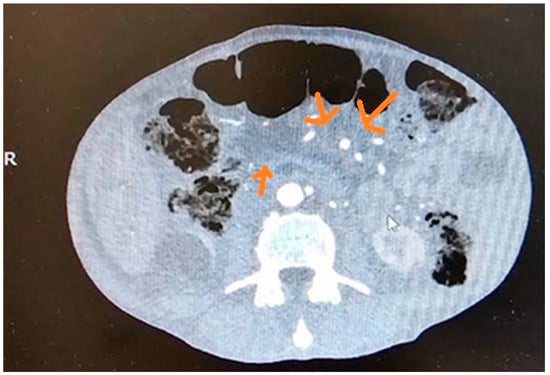

3.2. Computed Tomography (CT)

10.2. Computed Tomography (CT)